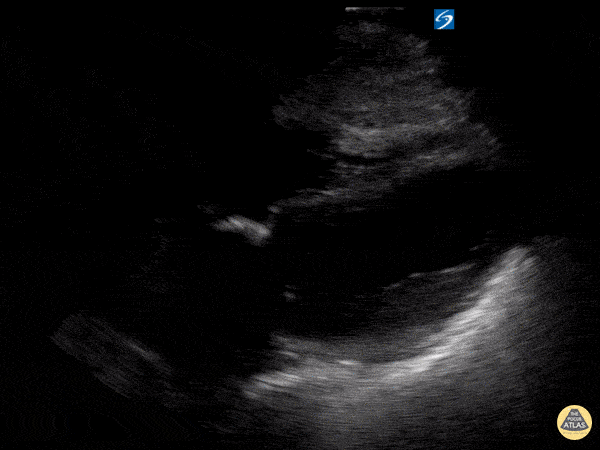

Apical Ballooning in takotsubo's cardiomyopathy

| current | 20:32, 7 January 2018 | 600 × 450 (417 KB) | Bobzmac (talk | contribs) | Apical Ballooning in Takotsubo's Cardiomyopathy http://www.thepocusatlas.com/left-ventricle-1 Submitted by Ilan Ben-Shabat, MS5 | |